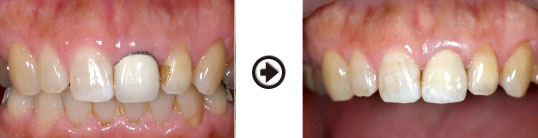

前歯にファイバーコアを入れ、オールセラミッククラウンを被せた症例

歯内療法をした後、グラスファイバー系のコア(土台)を入れました。利点として、歯根破折を起こしにくい、光の透過性が天然歯に近い、金属を使わないので歯肉に影ができないなど、美しく、自然な仕上がりとなります。